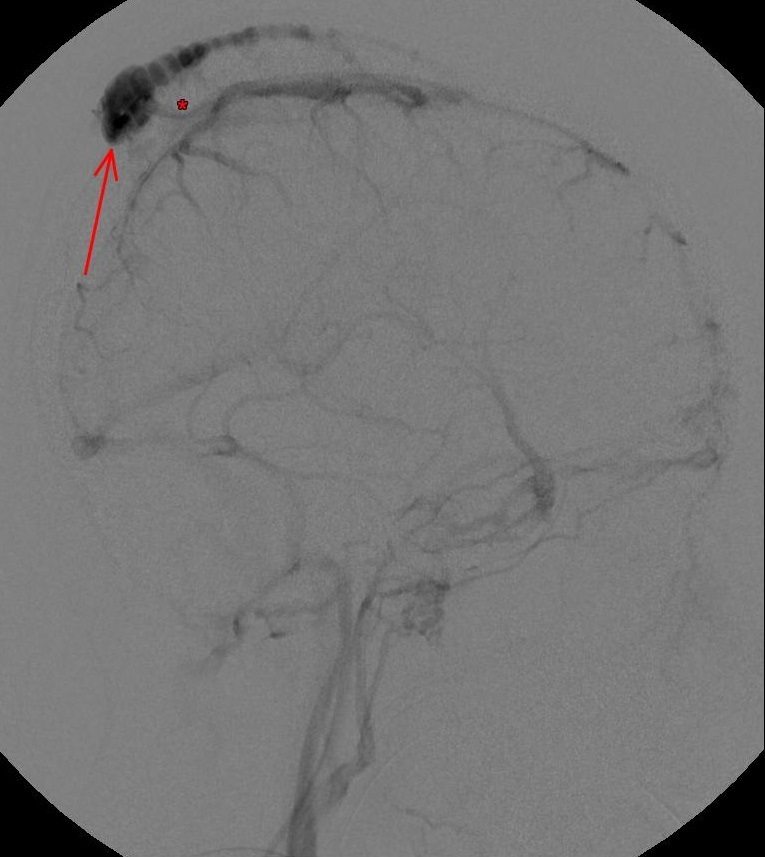

Über kleinste Mikrodrähte kann dann unter Röntgenkontrolle die Verbindungsvene im Schädelknochen sondiert werden, welche die inneren und äußeren blutableitenden Gefäße verbindet (linkes Angiogramm, *-Markierung). Über diese krankhafte Verbindung gelangt das Blut von der inneren Vene in die erweiterten äußeren Venen, welche die tastbare Schwellung verursachen (linkes Angiogramm, Pfeilmarkierung).

Ziel der Behandlung ist es, einen Verschluss der Verbindungsvene durch Platzierung von Platinspiralen zu erreichen (mittlere Aufnahme). In der abschließenden Kontrollaufnahme (rechtes Angiogramm) zeigt sich dann wieder ein physiologisches Bild der inneren Hirnvenen. Durch den Verschluss des Sinus pericranii wird der Druck auf die äußeren Venen deutlich verringert und die zuvor durch die Kopfhaut tastbare Schwellung geht zurück (Pfeilmarkierung). Somit besteht auch bei Kopfverletzungen an dieser Stelle kein erhöhtes Blutungsrisiko mehr.